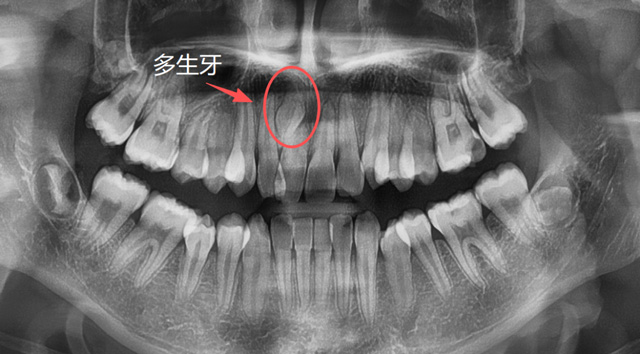

儿童上颌多生牙

建议家长在小朋友处于替牙期的时候,不管有没有牙疼,都找专业的口腔医生进行检查,必要时拍片看一下牙胚的数量有无出入,关注一下牙齿是否按正常的顺序完成了替换,如有异常情况,可以及时干预。

有些人因为牙列拥挤、乳牙滞留或先天发育等原因,恒牙没有在正常的位置萌出,反而往上颌窦、鼻腔等方向生长;称为“异位牙”,还有的牙因为全部或部分埋在了牙槽骨里,无法萌出,称为“阻生牙”,很多智齿就是这样的情况;还有一些超出正常数量的“多生牙”,通常也埋在牙槽骨里无法萌出。

那么,以上这些异常情况的牙都是天生的吗?能不能预防呢?

牙根的形态、数量是天生的,无法后天干预,但是对于部分异位牙、埋伏牙,我们可以在小朋友替牙期的这个阶段通过相应的医学手段来干预,避免一些成年后的拔牙。

长在上颌窦、鼻腔方向的异位牙,长在牙槽骨深处的多生牙,常常埋伏于骨内,需要骨开窗才能拔除,具有一定的难度。